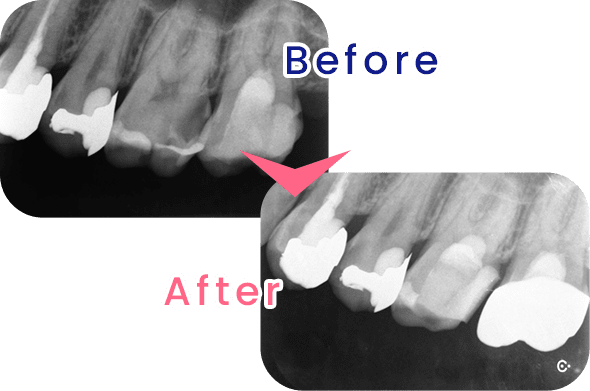

虫歯が歯髄(歯の神経)に達すると、歯髄を取る(抜髄)という処理が必要になりますが、こうした歯を残すことのできる、MTAセメントを使用した断髄という治療法が注目されています。断髄とは虫歯が進行したところまでの組織を取り除き、MTAセメントで蓋をすることにより、神経の生活反応を残したまま保存する方法です。

当院の虫歯治療